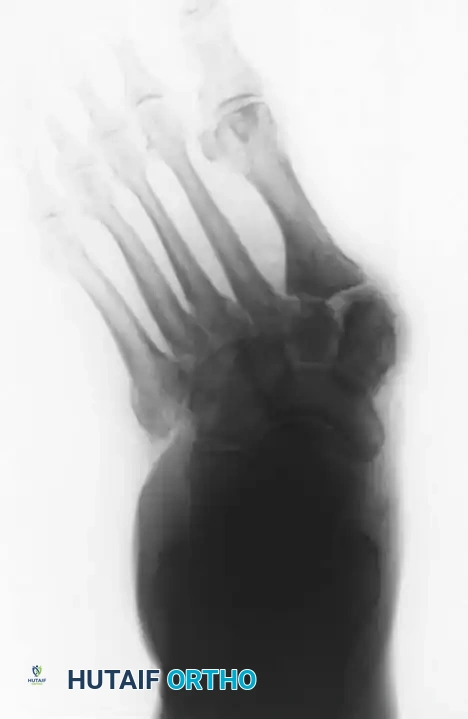

In the presence of motor neuropathy, the intrinsic musculature of the foot atrophies, leading to an intrinsic-minus foot posture. This results in the classic claw toe deformity: hyperextension at the metatarsophalangeal (MTP) joints and flexion at the proximal interphalangeal (PIP) joints. Consequently, the plantar fat pad is drawn distally, leaving the metatarsal heads prominent and unprotected against vertical and shear forces during the terminal stance phase of gait.

• Metatarsal Head Resection: Resection of one or more prominent metatarsal heads (or a complete pan-metatarsal head resection in severe cases) may be required to relieve plantar pressure and maintain ulcer closure.

* Type 1 (Midfoot): Involves the tarsometatarsal (Lisfranc) and naviculocuneiform joints. This is the most common pattern, affecting approximately 60% of patients. It frequently results in a rocker-bottom deformity.